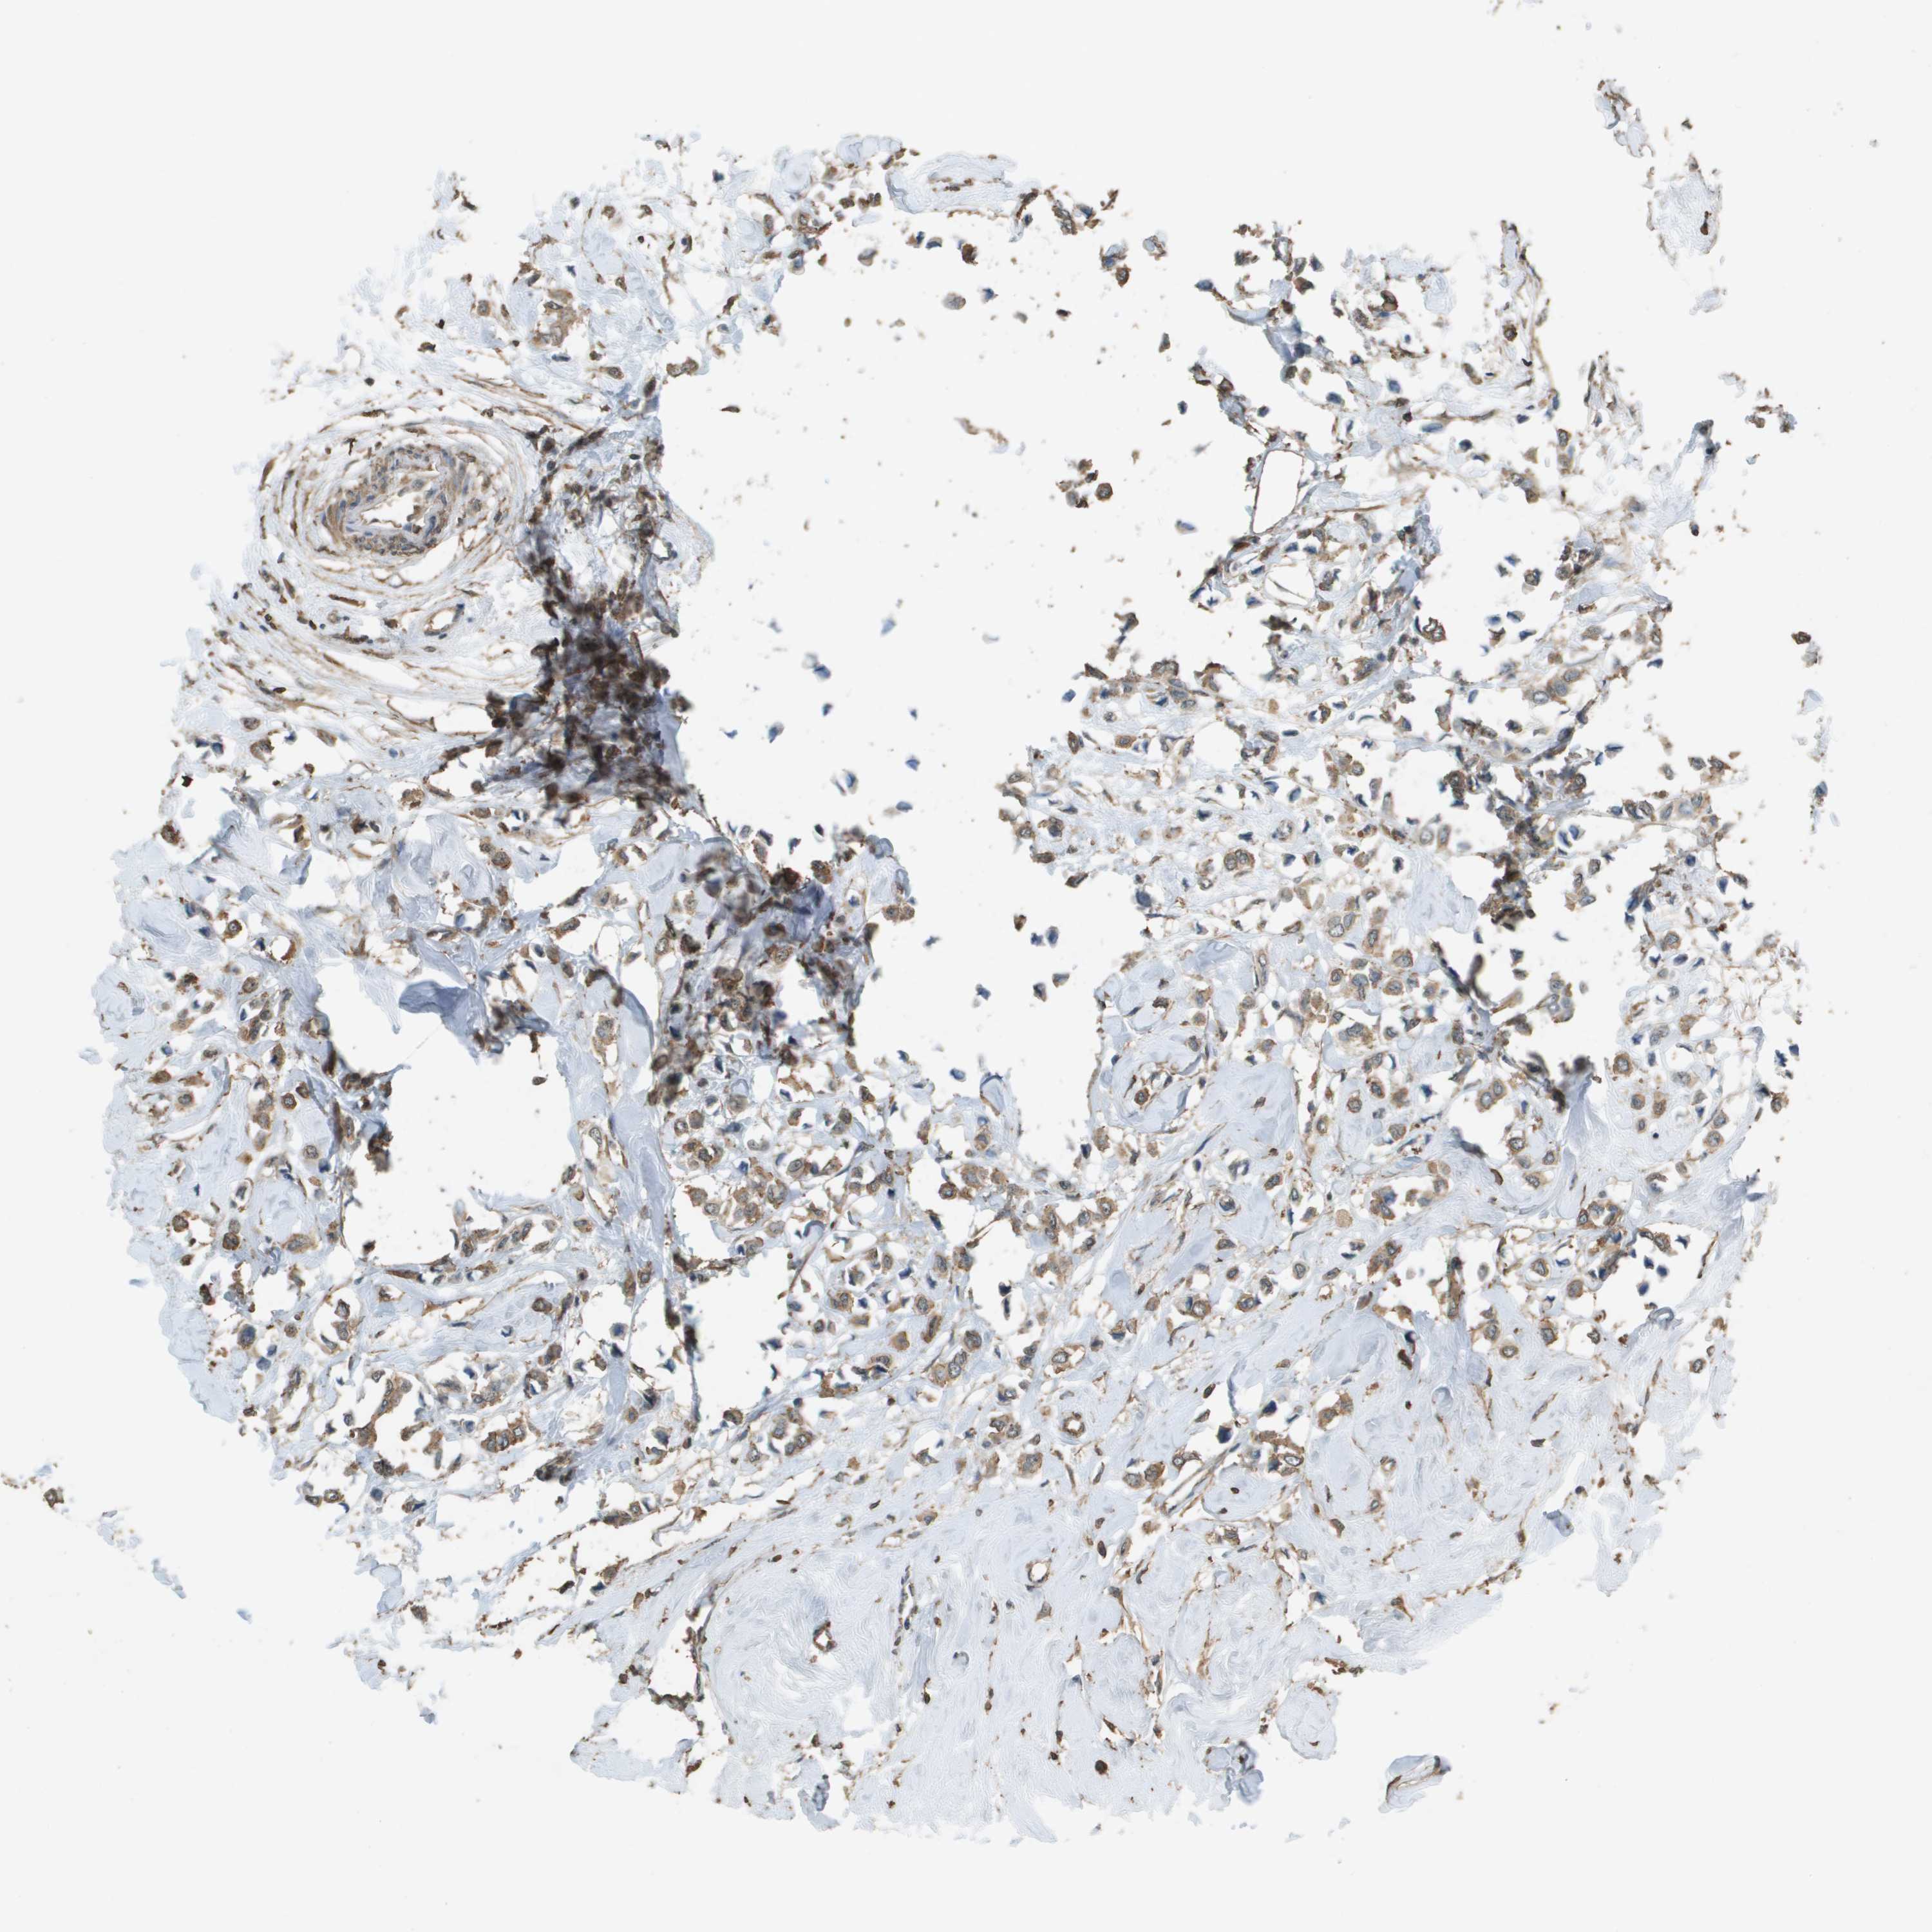

CANCER BREAST CANCER Show tissue menu

BRCA TCGA BRCA VALIDATION PROTEIN EXPRESSION

Breast cancer

Human cancer